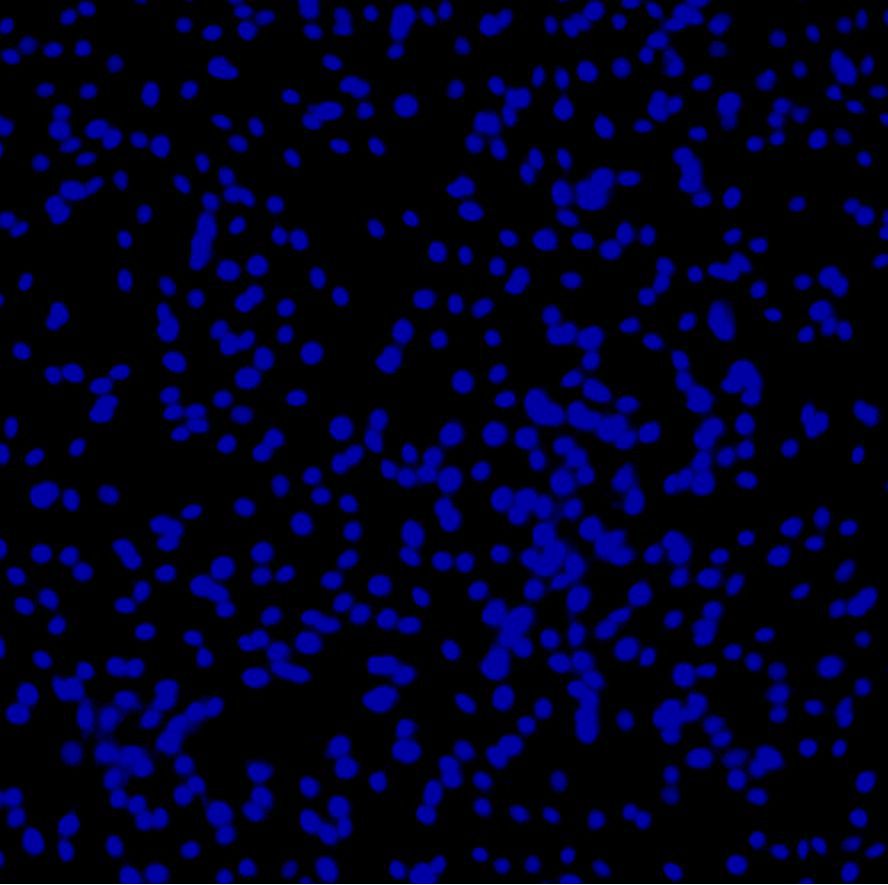

DAPI(4’,6-二脒基-2-苯基吲哚二盐酸盐)是一种能够与 DNA 中大部分 A,T 碱基相互结合的 荧光染料﹐常用于荧光显微镜观测。因为 DAPI 可以透过完整的细胞膜﹐它可以用于活细胞和固定 细胞的染色。当 DAPI 与双链 DNA 结合时,最大吸收波长为 358nm,最大发射波长为 461nm。DAPI 的发射光为蓝色,且 DAPI 和绿色荧光蛋白 GFP 或 Texas Red 染剂(红色荧光染剂)的发射波长仅有 少部分重叠,可以利用这项特性在单一的样品上进行多重荧光染色。 本产品为 DAPI 水溶液,纯度≥90%,为即用型工作液,可以直接用于固定细胞或组织的细胞 核染色。

5. 置于荧光显微镜下观察,激发波长 360-400nm。